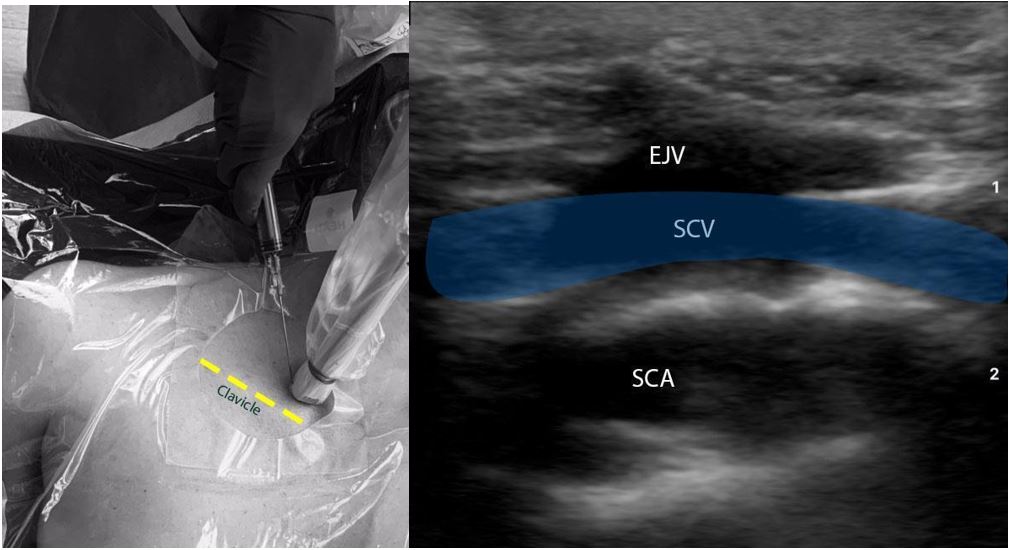

B. Supraclavicular in-plane approach (Figure 3):

- Position the patient in the Trendelenburg position to allow venous engorgement and minimize the risk of air embolism. The patient should be prepped and draped in the usual sterile fashion. The ipsilateral IJV should also be prepped and draped.

- Place the transducer in the supraclavicular fossa abutting the ipsilateral clavicle. Angle the probe anteriorly to visualize the supraclavicular SCV. Slide the probe medially along the linear course of SCV until it’s confluence with the IJV is visualized.

- Evaluate the depth, caliber, and patency of the SCV and IJV. Use compressibility and/or pulse-wave Doppler to confirm that the structure visualized is indeed the vein, and not the artery.

- Insert the needle in the in-plane approach. The needle should be advanced slowly under direct visualization. The lung pleura lies underneath the vessel and must be approached with caution.

- If needle visualization is lost, it is important to stop advancing the needle. Withdraw slightly and re-visualize the needle before proceeding.

- Once within the lumen of the vessel, insert the guidewire and monitor the guidewire placement in real time with ultrasound. The guidewire location in right atrium/ventricle can also be rapidly confirmed by a subxiphoid view of the heart.

- Make a small incision on the skin, dilate the vessel, and insert the catheter over the guidewire.

Figure 3: Ultrasound-guided subclavian vein cannulation. EJV (External Jugular Vein), SCV (subclavian vein), SCA (subclavian artery).